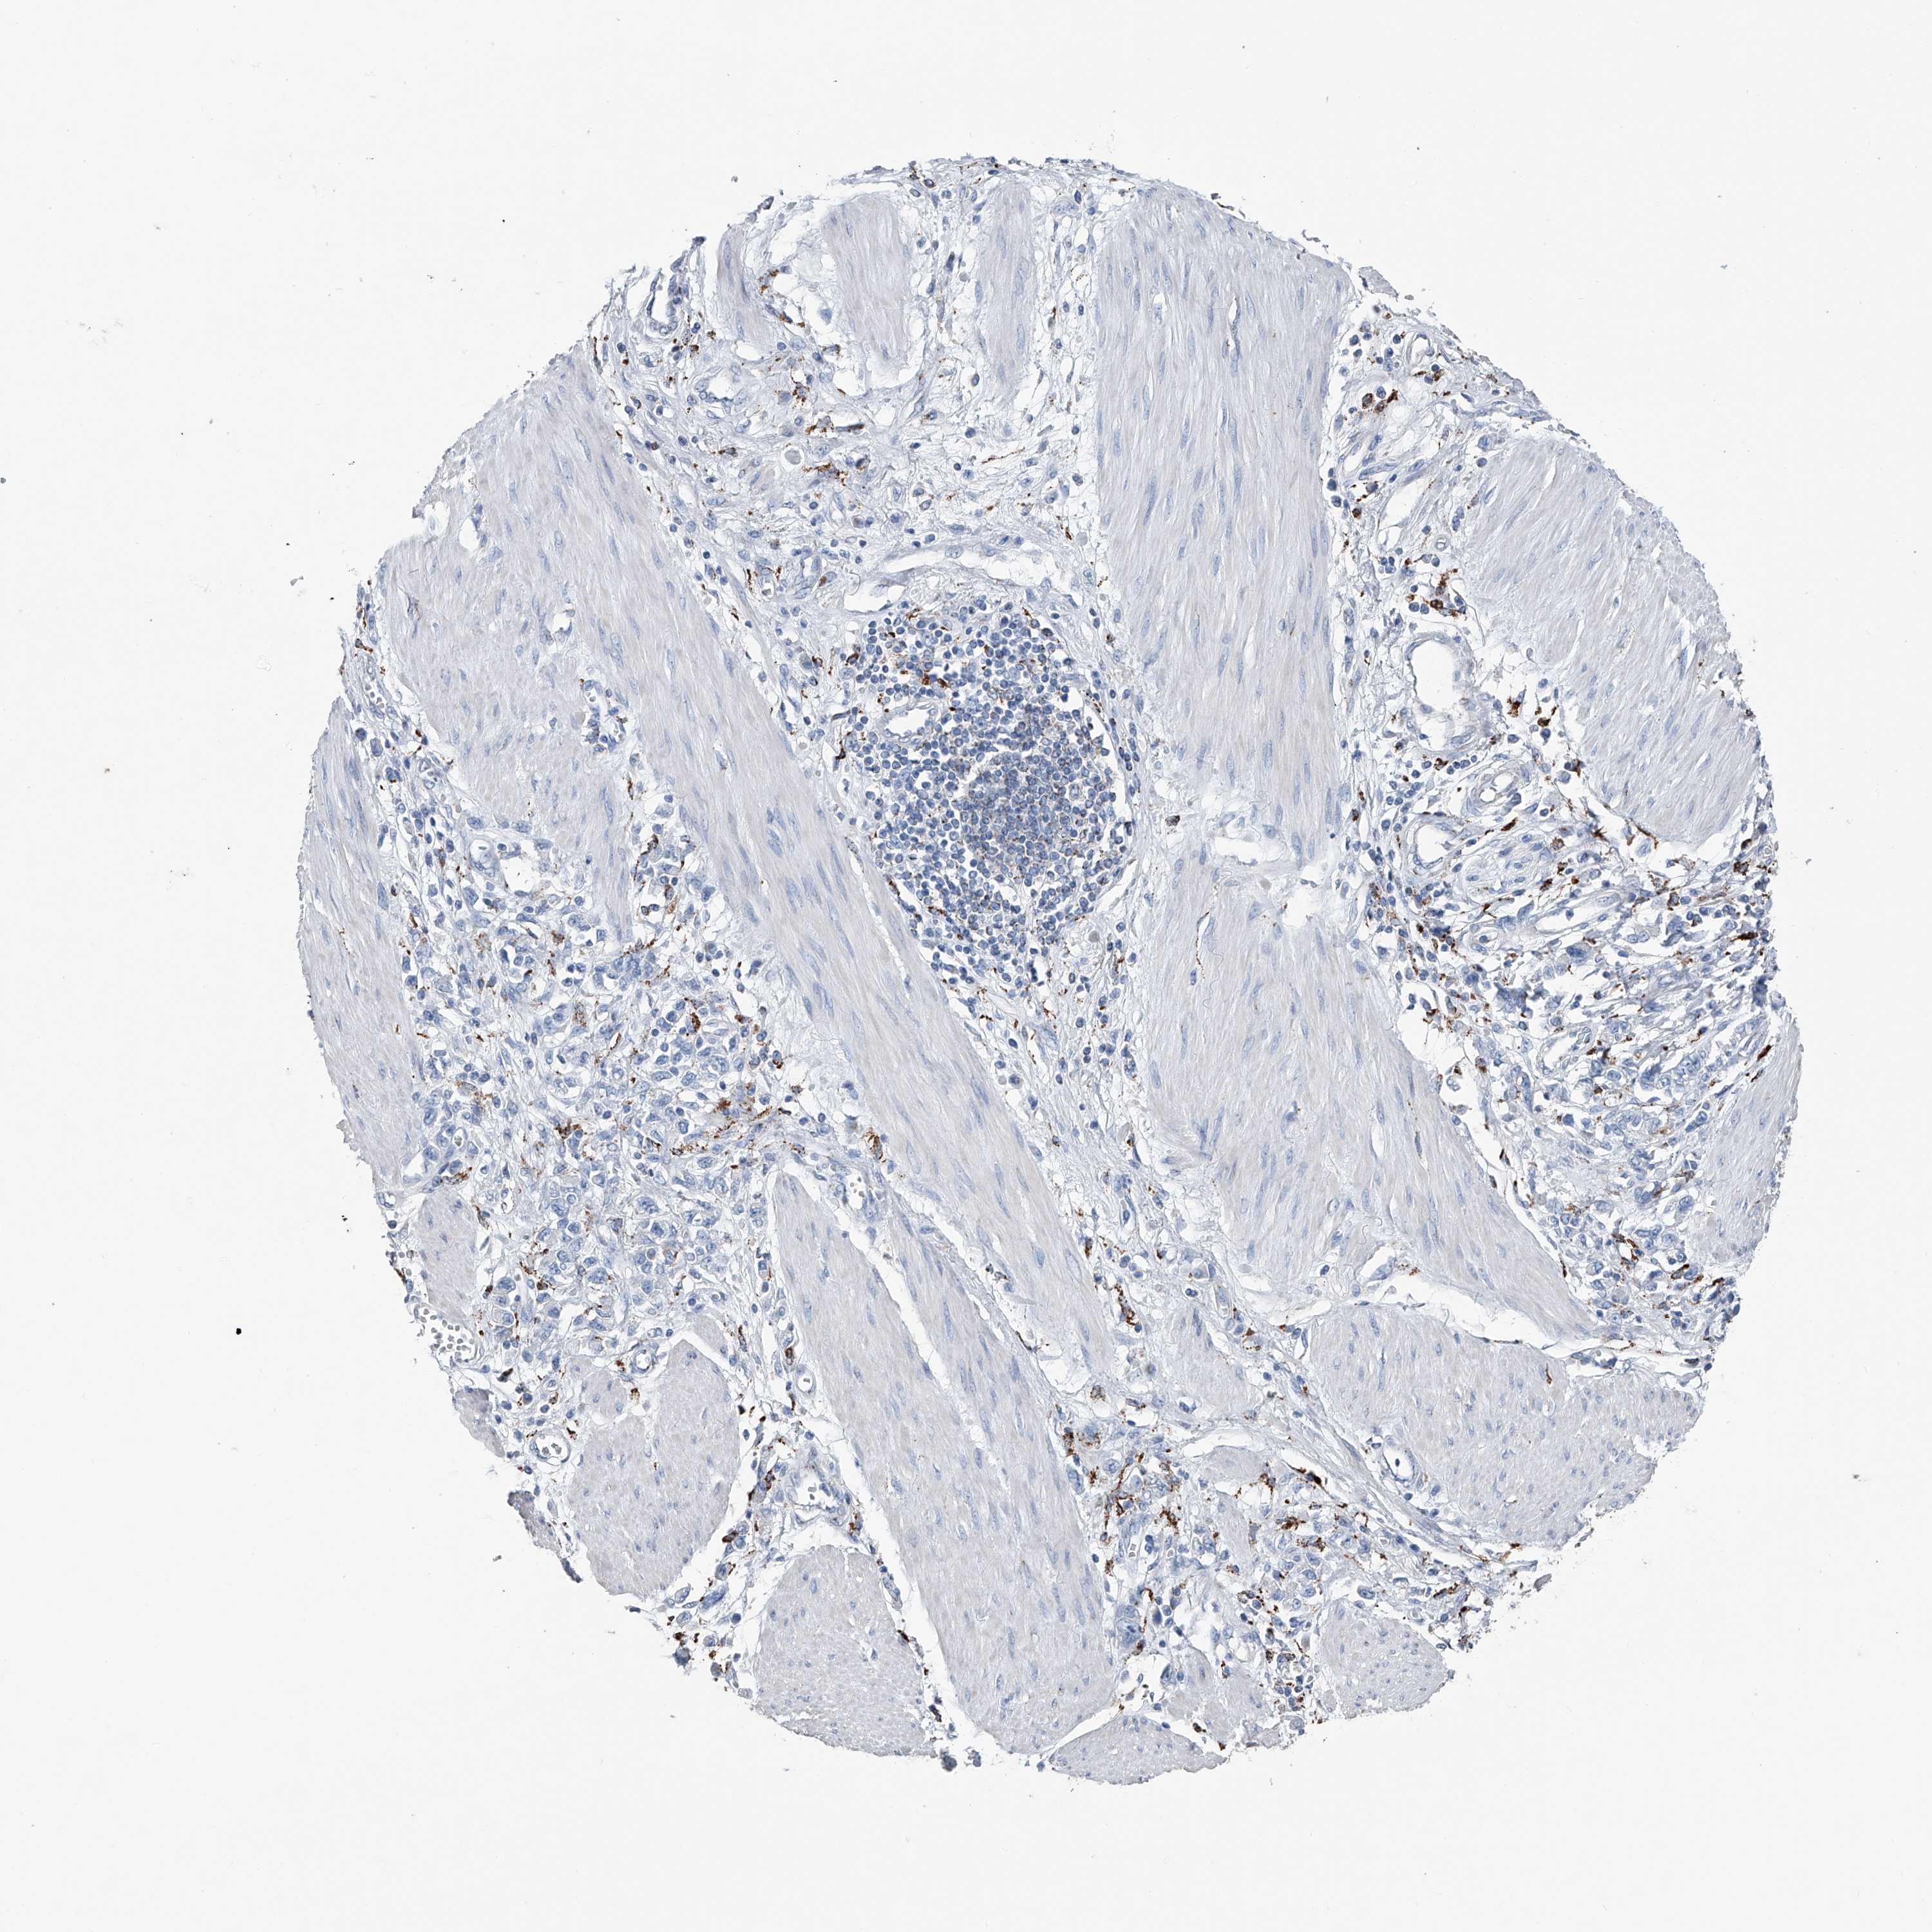

STOMACH CANCER - Protein expressioni

A mouse-over function shows sample information and annotation data. Click on an image to view it in a full screen mode. Samples can be filtered based on level of antibody staining by selecting one or several of the following categories: high, medium, low and not detected. The assay and annotation is described here.

Note that samples used for immunohistochemistry by the Human Protein Atlas do not correspond to samples in the TCGA dataset.

Antibody stainingi

Antibody staining in the annotated cell types in the current human tissue is reported as not detected, low, medium, or high, based on conventional immunohistochemistry profiling in selected tissues. This score is based on the combination of the staining intensity and fraction of stained cells.

Each image is clickable and will lead to virtual microscopy that enables deeper exploration of all samples and also displays staining intensity scores, fraction scores and subcellular localization as well as patient and tissue information for each sample.

Antibody HPA031312

Staining

High

Medium

Low

Not detected

Intensity

Strong

Moderate

Weak

Negative

Quantity

>75%

75%-25%

<25%

None

Location

Nuclear

Cytoplasmic/membranous

Cytoplasmic/membranous,nuclear

Adenocarcinoma, NOS